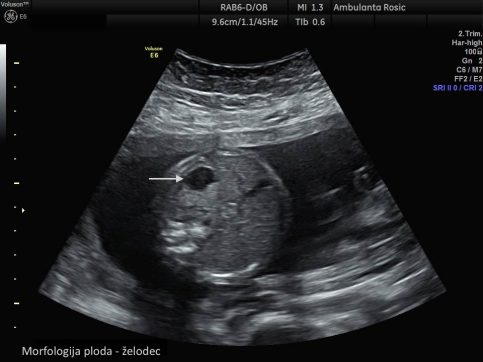

Morfologija ploda

Z morfologijo ploda ugotavljamo normalen razvoj ploda. Ultrazvočni pregled morfologije ploda izvajamo med 19. in 23. tednom nosečnosti. Namenjen je ugotavljanju plodove gestacijske starosti in oceni plodove rasti z merjenjem glavice, trebuha in stegenske kosti ploda ter odkrivanju večjih in manjših razvojnih nepravilnosti pri plodu, ki so povezane s kromosomskimi napakami. S preiskavo opravimo natančen pregled in oceno razvoja ploda in njegovih organov. Pregledamo strukture v glavici, hrbtenico, prsnegi koš, trebuh in okončine ploda. Posebno pozornost namenimo pregledu plodovega srca. Določimo položaj ploda v maternici. Pregledamo tudi posteljico in popkovnico ter ocenimo količino plodovnice. V večini primerov lahko s preiskavo ugotovimo tudi plodov spol, ki pa ga razkrijemo le, če to želite.